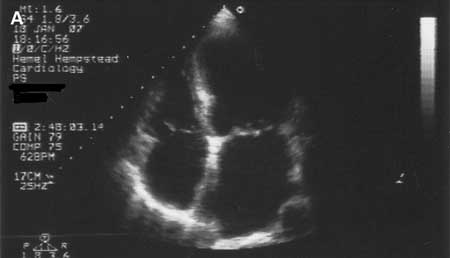

Cardiomiopatia dilatada: ecocardiografia

Tanejal AK, Wong J, Bayliss J. Antipsychotic-drug-induced dilated cardiomyopathy. BMJ Case Reports. 2009; doi:10.1136/bcr.09.2008.0958